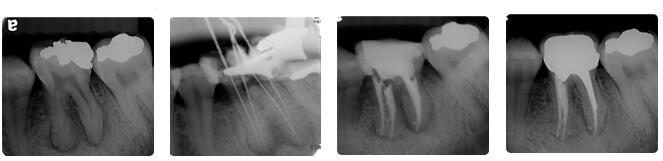

根管治疗通常包括三个基本步骤:根管预备、根管消毒、根管充填。

首先会解决根管内的炎症牙髓和坏死物质,接下来测量根管长度,并适当扩大根管(即根管预备过程),然后在根管内封药消毒,最后用药物充填根管。

根管治疗时,拍牙片是很有必要的,并且至少要保障3张牙片。

第一张在治疗前,帮助医生了解牙根的基本情况,制定治疗计划;

第二张在治疗中,帮助医生了解治疗情况,如根管预备是否到位等,并制定下一步治疗方案;

第三张是在治疗结束后,帮助判定根管充填质量,发现问题及时补救。